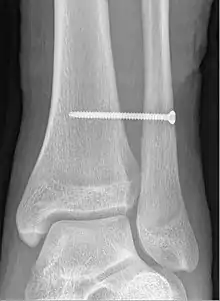

X-ray of a syndesmotic screw in place.

A syndesmotic screw is a metal screw designed to replace the syndesmosis of the human body, usually temporarily. If the syndosmosis is torn apart as result of bone fracture, surgeons will sometimes fix the relevant bones together with a syndesmotic screw, temporarily replacing the normal articulation.

A syndesmotic screw designed to replace the inferior tibiofibular articulation that fix the tibia and fibula together at the lower joint, is 5–6 cm long and made of a stainless, solid metal.